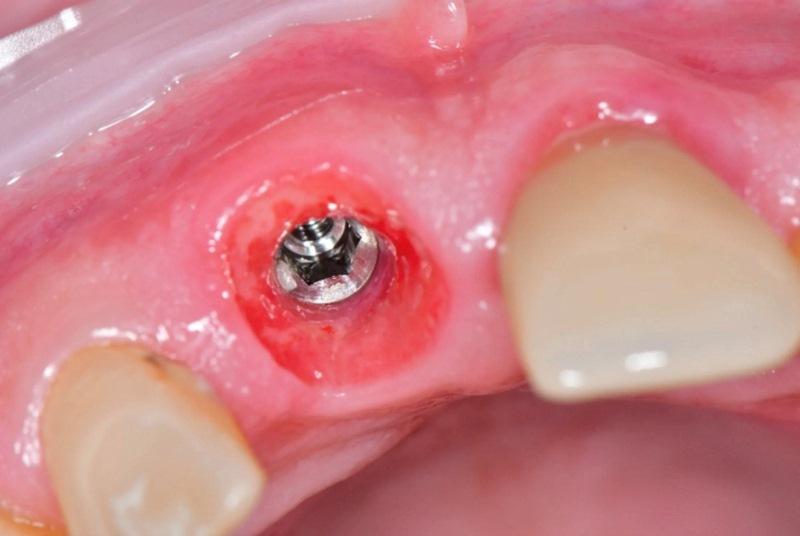

Хирургический шаблон введен в полость рта для проверки посадки относительно соседних зубов и стабильности на дуге. Остеотомия выполнена с применением направляемого хирургического набора (Ritter Guided Kit, Ritter Implants) через шаблон для немедленной установки имплантата в область зуба 1.1. Стартовая остеотомия выполнена пилотным сверлом 2,8 мм из направляемого набора (Ritter Implants), введенным через шаблон для обеспечения точной ориентации и позиционирования. Далее проведена оссеоденсификация борами Densah (Versah), в частности 3,0 и 3,5 мм, в обратном режиме (против часовой стрелки) согласно протоколу производителя, при 1 200 об/мин с обильной ирригацией физиологическим раствором. Имплантат (Spiral SB/LA Implant, 4,2×13 мм, Ritter Implants) установлен через хирургический шаблон в полости рта с позиционированием на 3 мм ниже уровня гребня. Вкручивание достигнуто при моменте 25 Н·см. Индивидуальный формирователь десны подготовлен и отложен до этапа установки.

Аллотрансплантат MinerOss (BioHorizons) смешан с PRF, полученным в начале приема, для изготовления смеси «липкая кость». Смесь введена для заполнения гребневых щелей между стенками лунки и имплантатом. Затем на имплантат установлен индивидуальный формирователь десны.